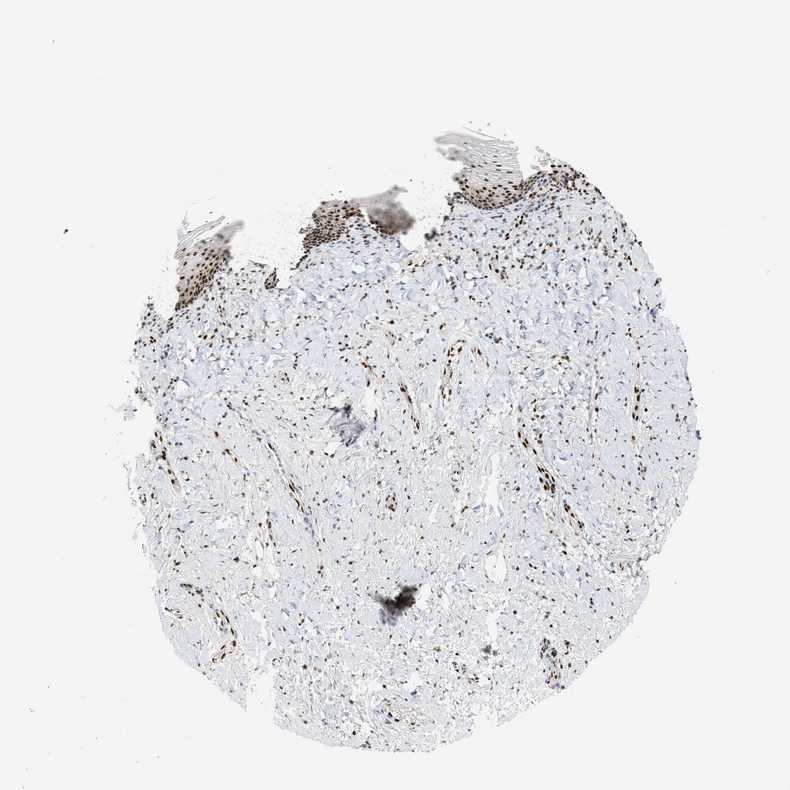

VAGINA - Antibody stainingi

Antibody staining in the annotated cell types in the current human tissue is reported as not detected, low, medium, or high, based on conventional immunohistochemistry profiling in selected tissues. This score is based on the combination of the staining intensity and fraction of stained cells.

Each image is clickable and will lead to virtual microscopy that enables deeper exploration of all samples and also displays staining intensity scores, fraction scores and subcellular localization as well as patient and tissue information for each sample.

Antibody HPA022961Antibody HPA024457

Squamous epithelial cells HighHigh